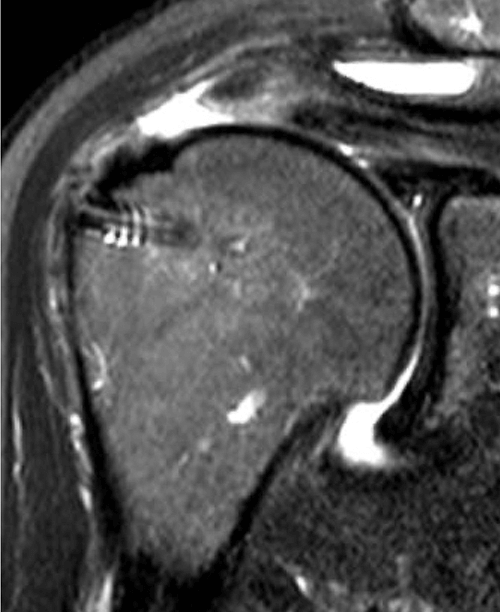

This is one of my cases, a 55-year-old woman, when her primary rotator cuff repair was done, we used Dermis on Demand, which is an allograft skin that can be utilized to help strengthen repairs. At four months out, the patient presented with pain and weakness following a traumatic injury and wound up re-tearing.

You can see a clear retear to the rotator cuff here with slight retraction, and some degeneration and thickness to the tendon.

We published this case study in the JOEI (Journal of Orthopedic Experience and Innovation) Journal. We did a revision of the large type-II repair and augmented it with BioBrace®. You can see the pre-op and three-month MRI below. Still fluid in the subacromial space but that tendon is clearly coming across into the footprint. Then, an eight-month MRI shows there's no further fluid in the subacromial space and maturation of that repair across the footprint.

Pre-OP

3 Months

8 Months